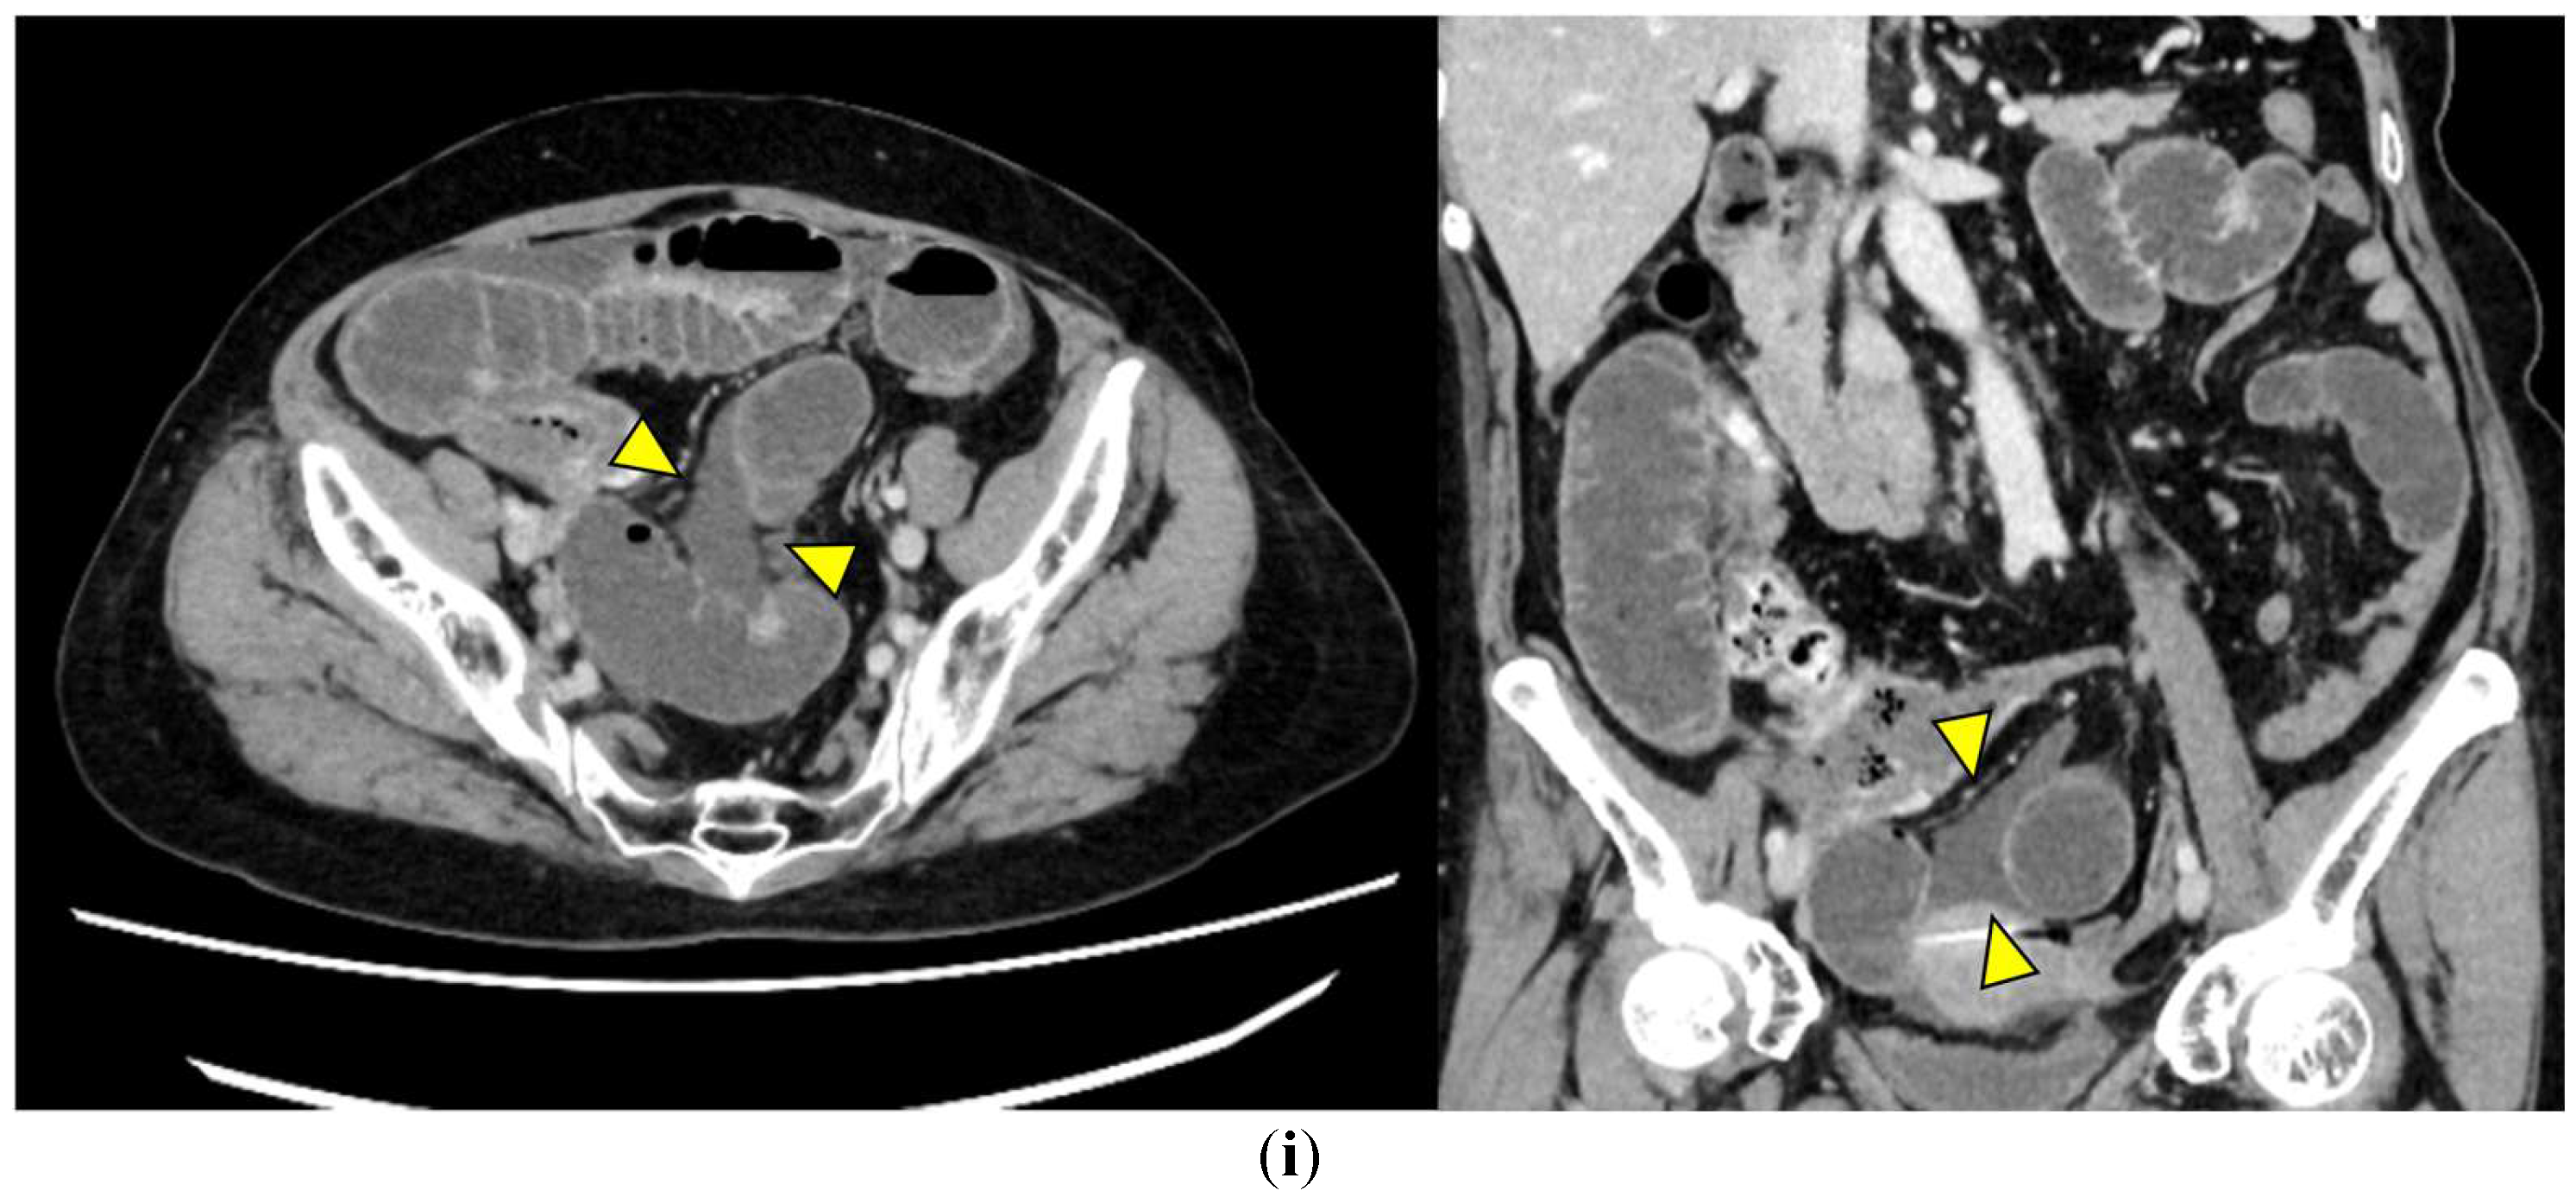

• Ascites (Figure 1i): Free peritoneal fluid, either localized around the affected loop or diffusely distributed, is frequently associated with advanced ischemia. Increasing ascites in the obstruction setting often indicates transmural ischemia or severe inflammation.

Figure 1. Representative CT findings suggestive of SSBO. Yellow arrowheads highlight the relevant findings. (a) Closed loop; (b) beak sign; (c) whirl sign; (d) small bowel feces sign; (e) mesenteric edema; (f) mesenteric vessel engorgement; (g) absent bowel wall enhancement; (h) blurred Kerckring folds; (i) ascites.